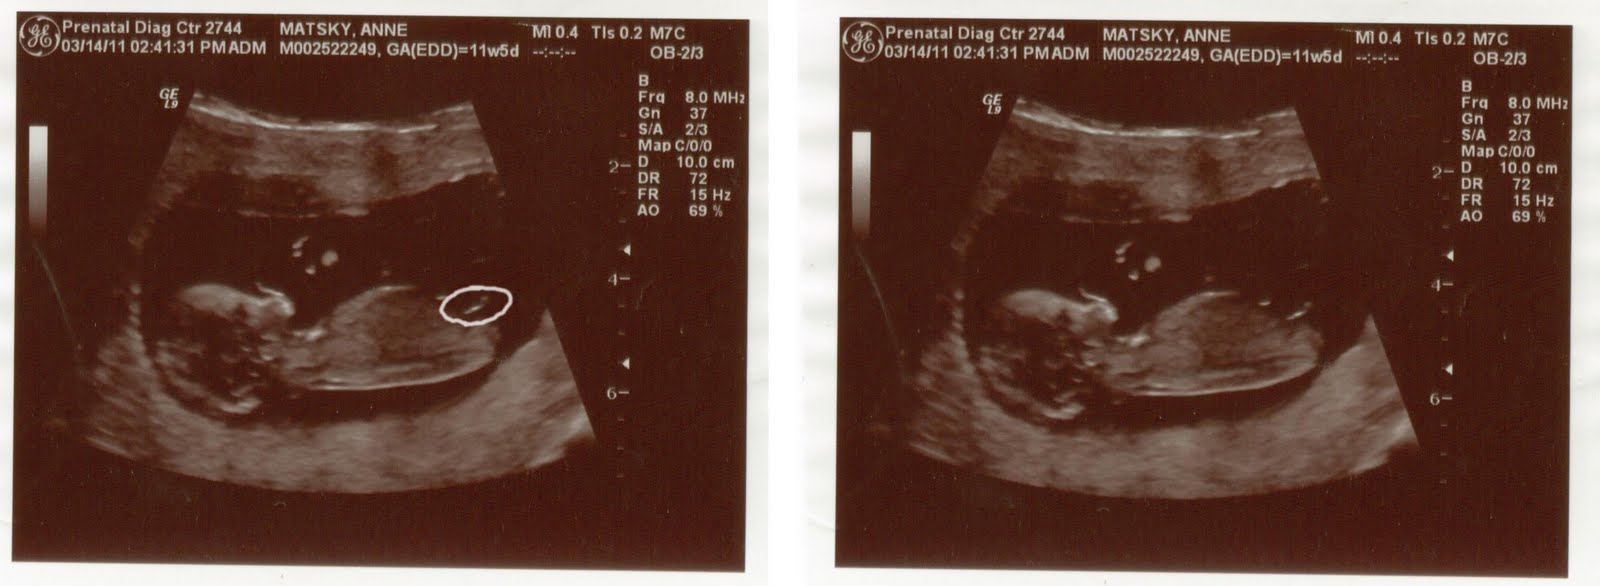

Second ultrasound, baby's profile - 11 weeks & 5 days (baby measured 12 weeks & 3 days)